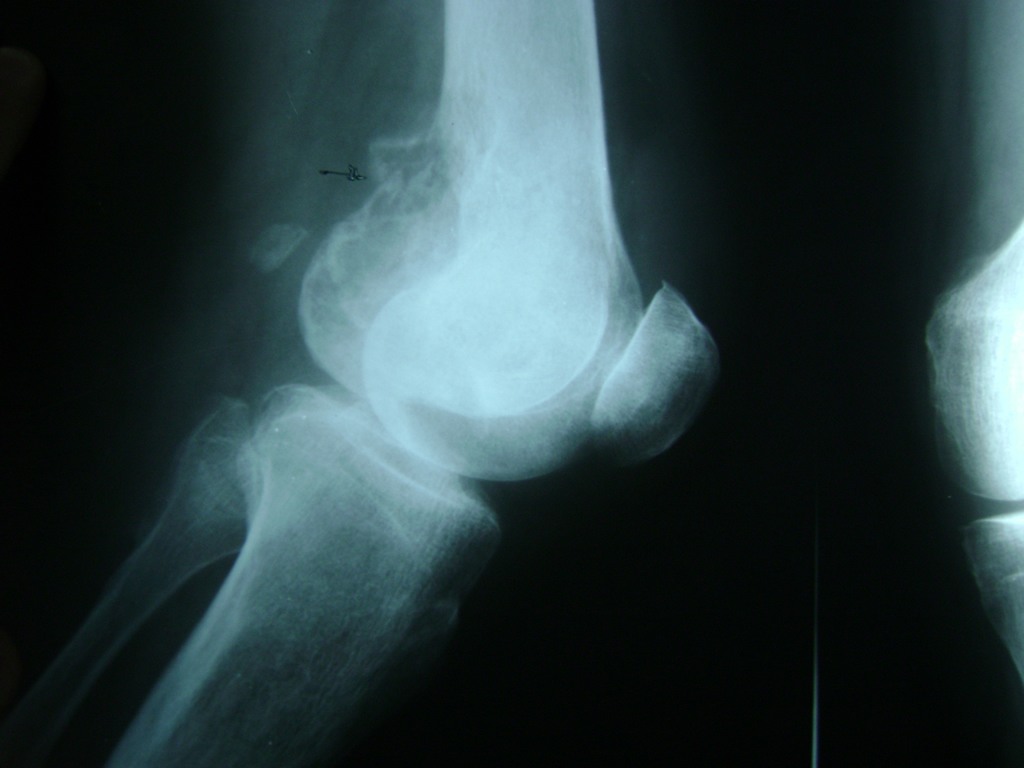

Cirugía de Fémur - Rodilla